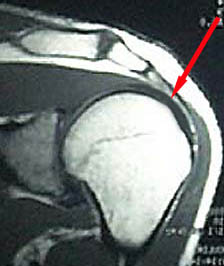

Torn Rotator Cuff MRI